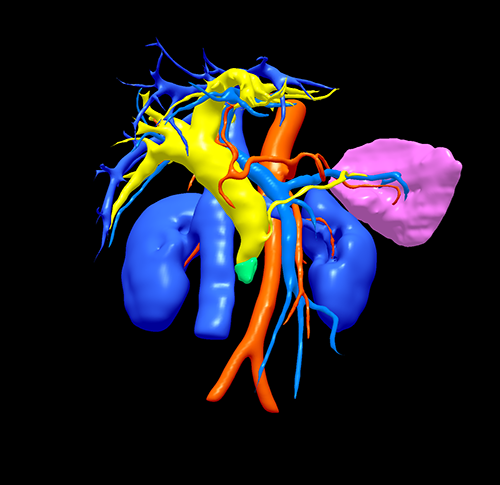

胰头癌-胰十二指肠切除